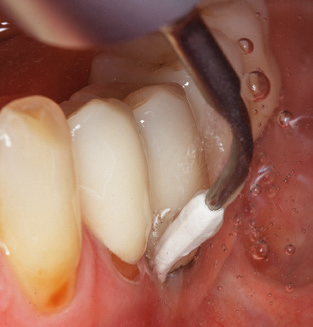

Fig. 4: Flexible probes with millimetre markings are recommended for the probing of dental implants (e.g. Colorvue Kit PCV11KIT6, Hu­Friedy). – Fig. 5a and b: A straight working tip (1P, W&H Dentalwerk Bürmoos GmbH) is a suitable instrument for use on all natural teeth. – Fig. 6: Curved working tips (3Pr/3Pl, W&H Dentalwerk Bürmoos GmbH) lend themselves to the processing of difficult-to-reach areas of the tooth and root surfaces (e.g. furcations). – Fig. 7: The tapered, hexagonal implant cleaning tip (1I, W&H Dentalwerk Bürmoos GmbH) permits atraumatic and efficient cleaning of the crown and abutment surfaces. – Fig. 8: Titanium and carbon curettes are suitable instruments for the manual cleaning of the implant surfaces.

Good illumination of the working field facilitates the process considerably. The system used by the authors achieves this thanks to a 5x LED ring integrated in the handpiece. Naturally, a range of working tips for different indications is also offered. A straight, universally employable tip is the basic instrument required for machine cleaning of natural teeth (Fig. 5a and b). Curved tips, which allow access to exposed furcations, are also available for hard-to-reach areas in the posterior region (Fig. 6).